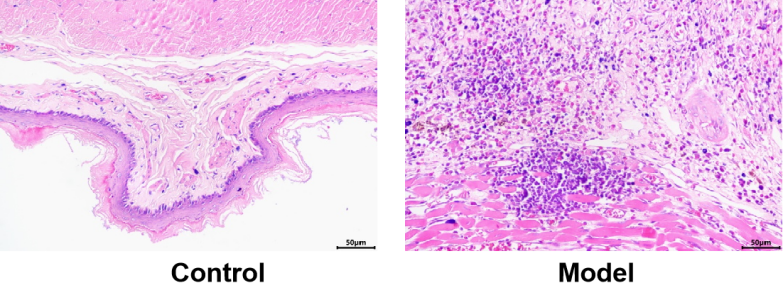

模型验证:与对照组相比,模型组食管粘膜粗糙,细胞炎症浸润情况严重,表明模型成功。

图2 HE模型验证(200X)